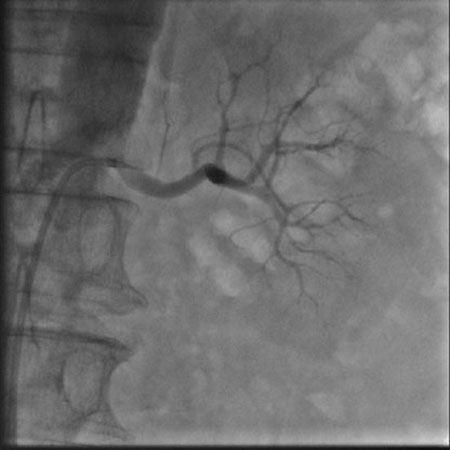

肾动脉造影(左)

2月6日,我院心内科在上海普陀区中心医院心内科刘宗军主任指导下开展了我省首例肾动脉交感神经射频消融术。目前患者病情稳定,一周后复查动态血压,平均收缩压已从术前157mmHg降至137mmHg,患者已出院在继续随访中。

肾动脉交感神经射频消融术用于难治性高血压的治疗,于2008年在美国首先应用于临床,属介入手术,只需穿刺肾动脉进行手术,治疗完成后1—3月内患者血压即可明显下降,最大降幅可达30—40mmHg。术后患者服用少量降压药物即可将血压控制在良好水平,部分患者可以永久摆脱降压药物。从而避免了终生服用降压药带来的经济负担、生活不便和副作用影响。